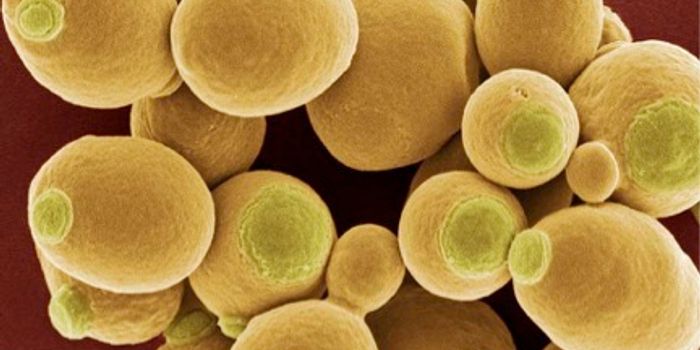

FEB 13, 2018Clinical & Molecular DXDiagnosing a dangerous infection by a fungal yeast that often devastates hospital patients is now faster and more effici ...

MAY 19, 2017MicrobiologyCandida auris is often resistant to most antibiotic treatments.